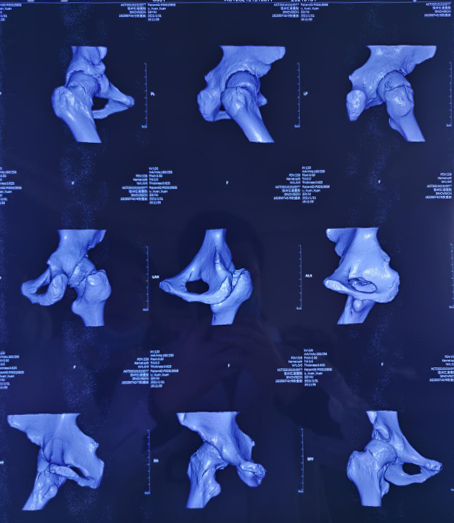

术前影像

关节科、运动医学科张传开主任给患者完善相关检查,该患者的各项指征符合进行股骨颈骨折机器人手术的要求。